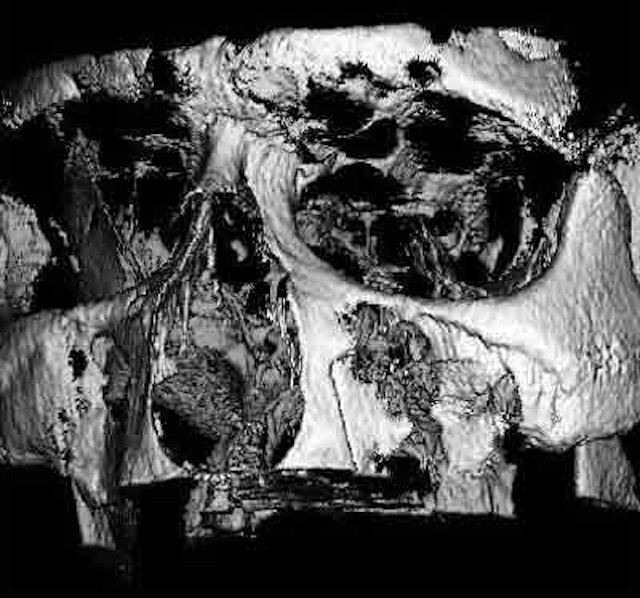

Der digitale Volumentomograph eröffnet für die Zahnheilkunde neue diagnostische Möglichkeiten. Wir setzen hier ein Gerät der Fa. Morita ein, das es ermöglicht auch kleine Aufnahmefelder (4*4 cm) zu tomographieren. Damit ist eine erhebliche Reduktion der Strahlenbelastung verbunden gegenüber Geräten, die nur große Aufnahmefelder untersuchen können. Wir nutzen diese Diagnostik für die Darstellung krankhafter Prozesse im Kiefer-Gesichtsbereich und für die Implantatplanung. Selbst für die Diagnostik vor Weisheitszahnentfernung kann eine solche Aufnahme sinnvoll sein, z.B. wenn die Gefahr einer besonderen Nervnähe besteht oder im Ramen einer Wurzelbehandlung wenn die Anatomie sich nicht durch zweidimensionale Aufnamen klären lässt.

Hier verläuft der Nervkanal direkt durch den Weisheitszahn. Dieser Befund kann nur durch die zweite Ebene gesichert werden. Das DVT erlaubt eine sichere Diagnostik und hilft, sicher zu entscheiden.